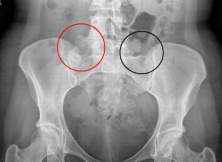

Dùng thuốc điều trị viêm khớp cùng chậu (12/10/2012)

Viêm khớp cùng chậu là một bệnh khớp viêm...